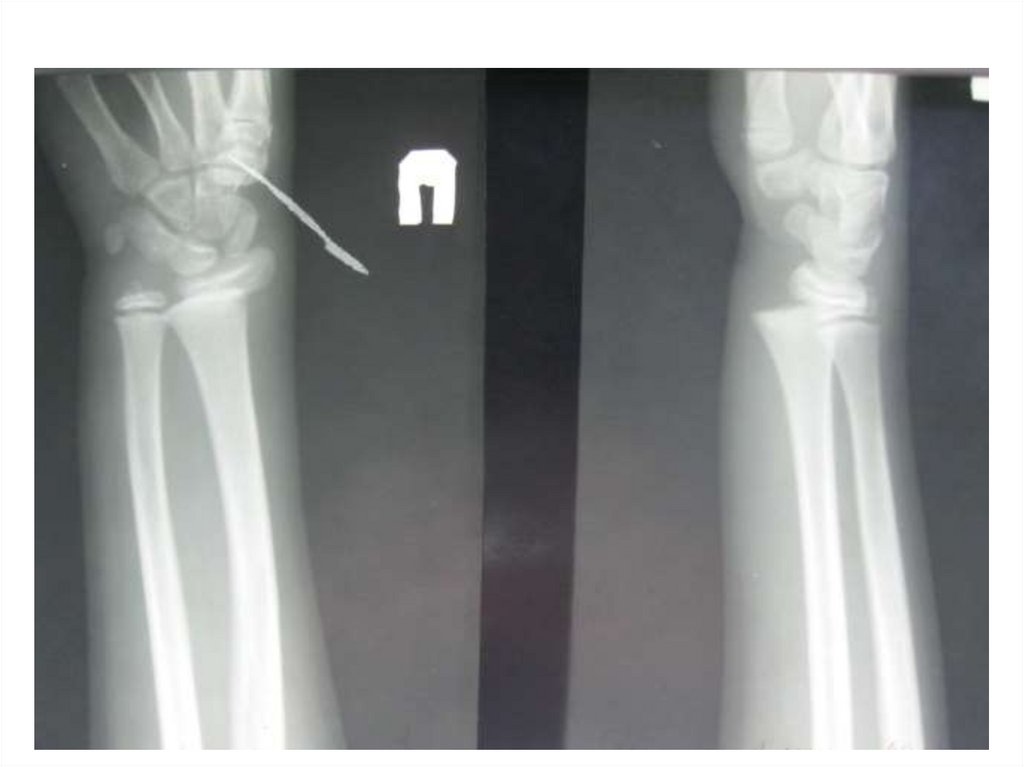

Назовите

• Вид исследования

• Область исследования

• Патологию